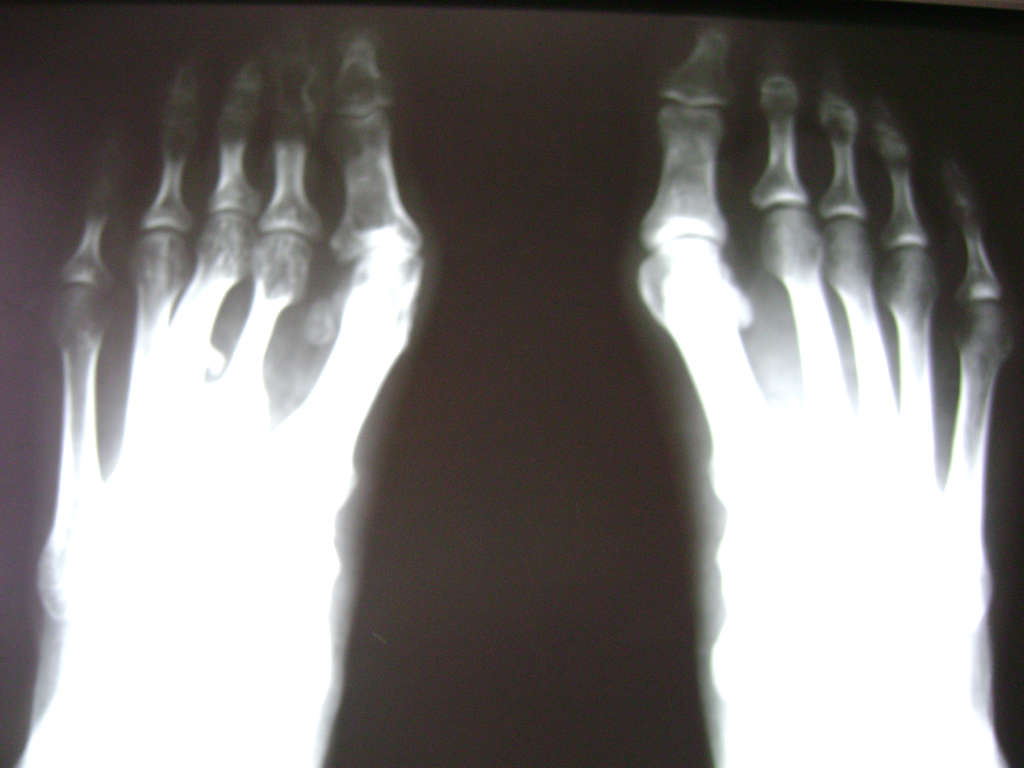

Las deformidades de los pies heredadas o adquiridas son el objeto principal de la cirugía reconstructiva del pie; sobretodo cuando producen dolor con el apoyo debido a una sobrecarga localizada o bien al no ser capaces de adaptarse a un calzado apropiado.

El pie consta de numerosas articulaciones con un mínimo movimiento cuya finalidad es adaptarse al terreno en cualquier situación. Cuando estas articulaciones que soportan grandes cargas y realizan movimientos sutiles se deterioran o funcionan de manera inapropiada, se suelen fusionar con el fin de evitar el dolor o bien restablecer la forma natural del pie y del apoyo.